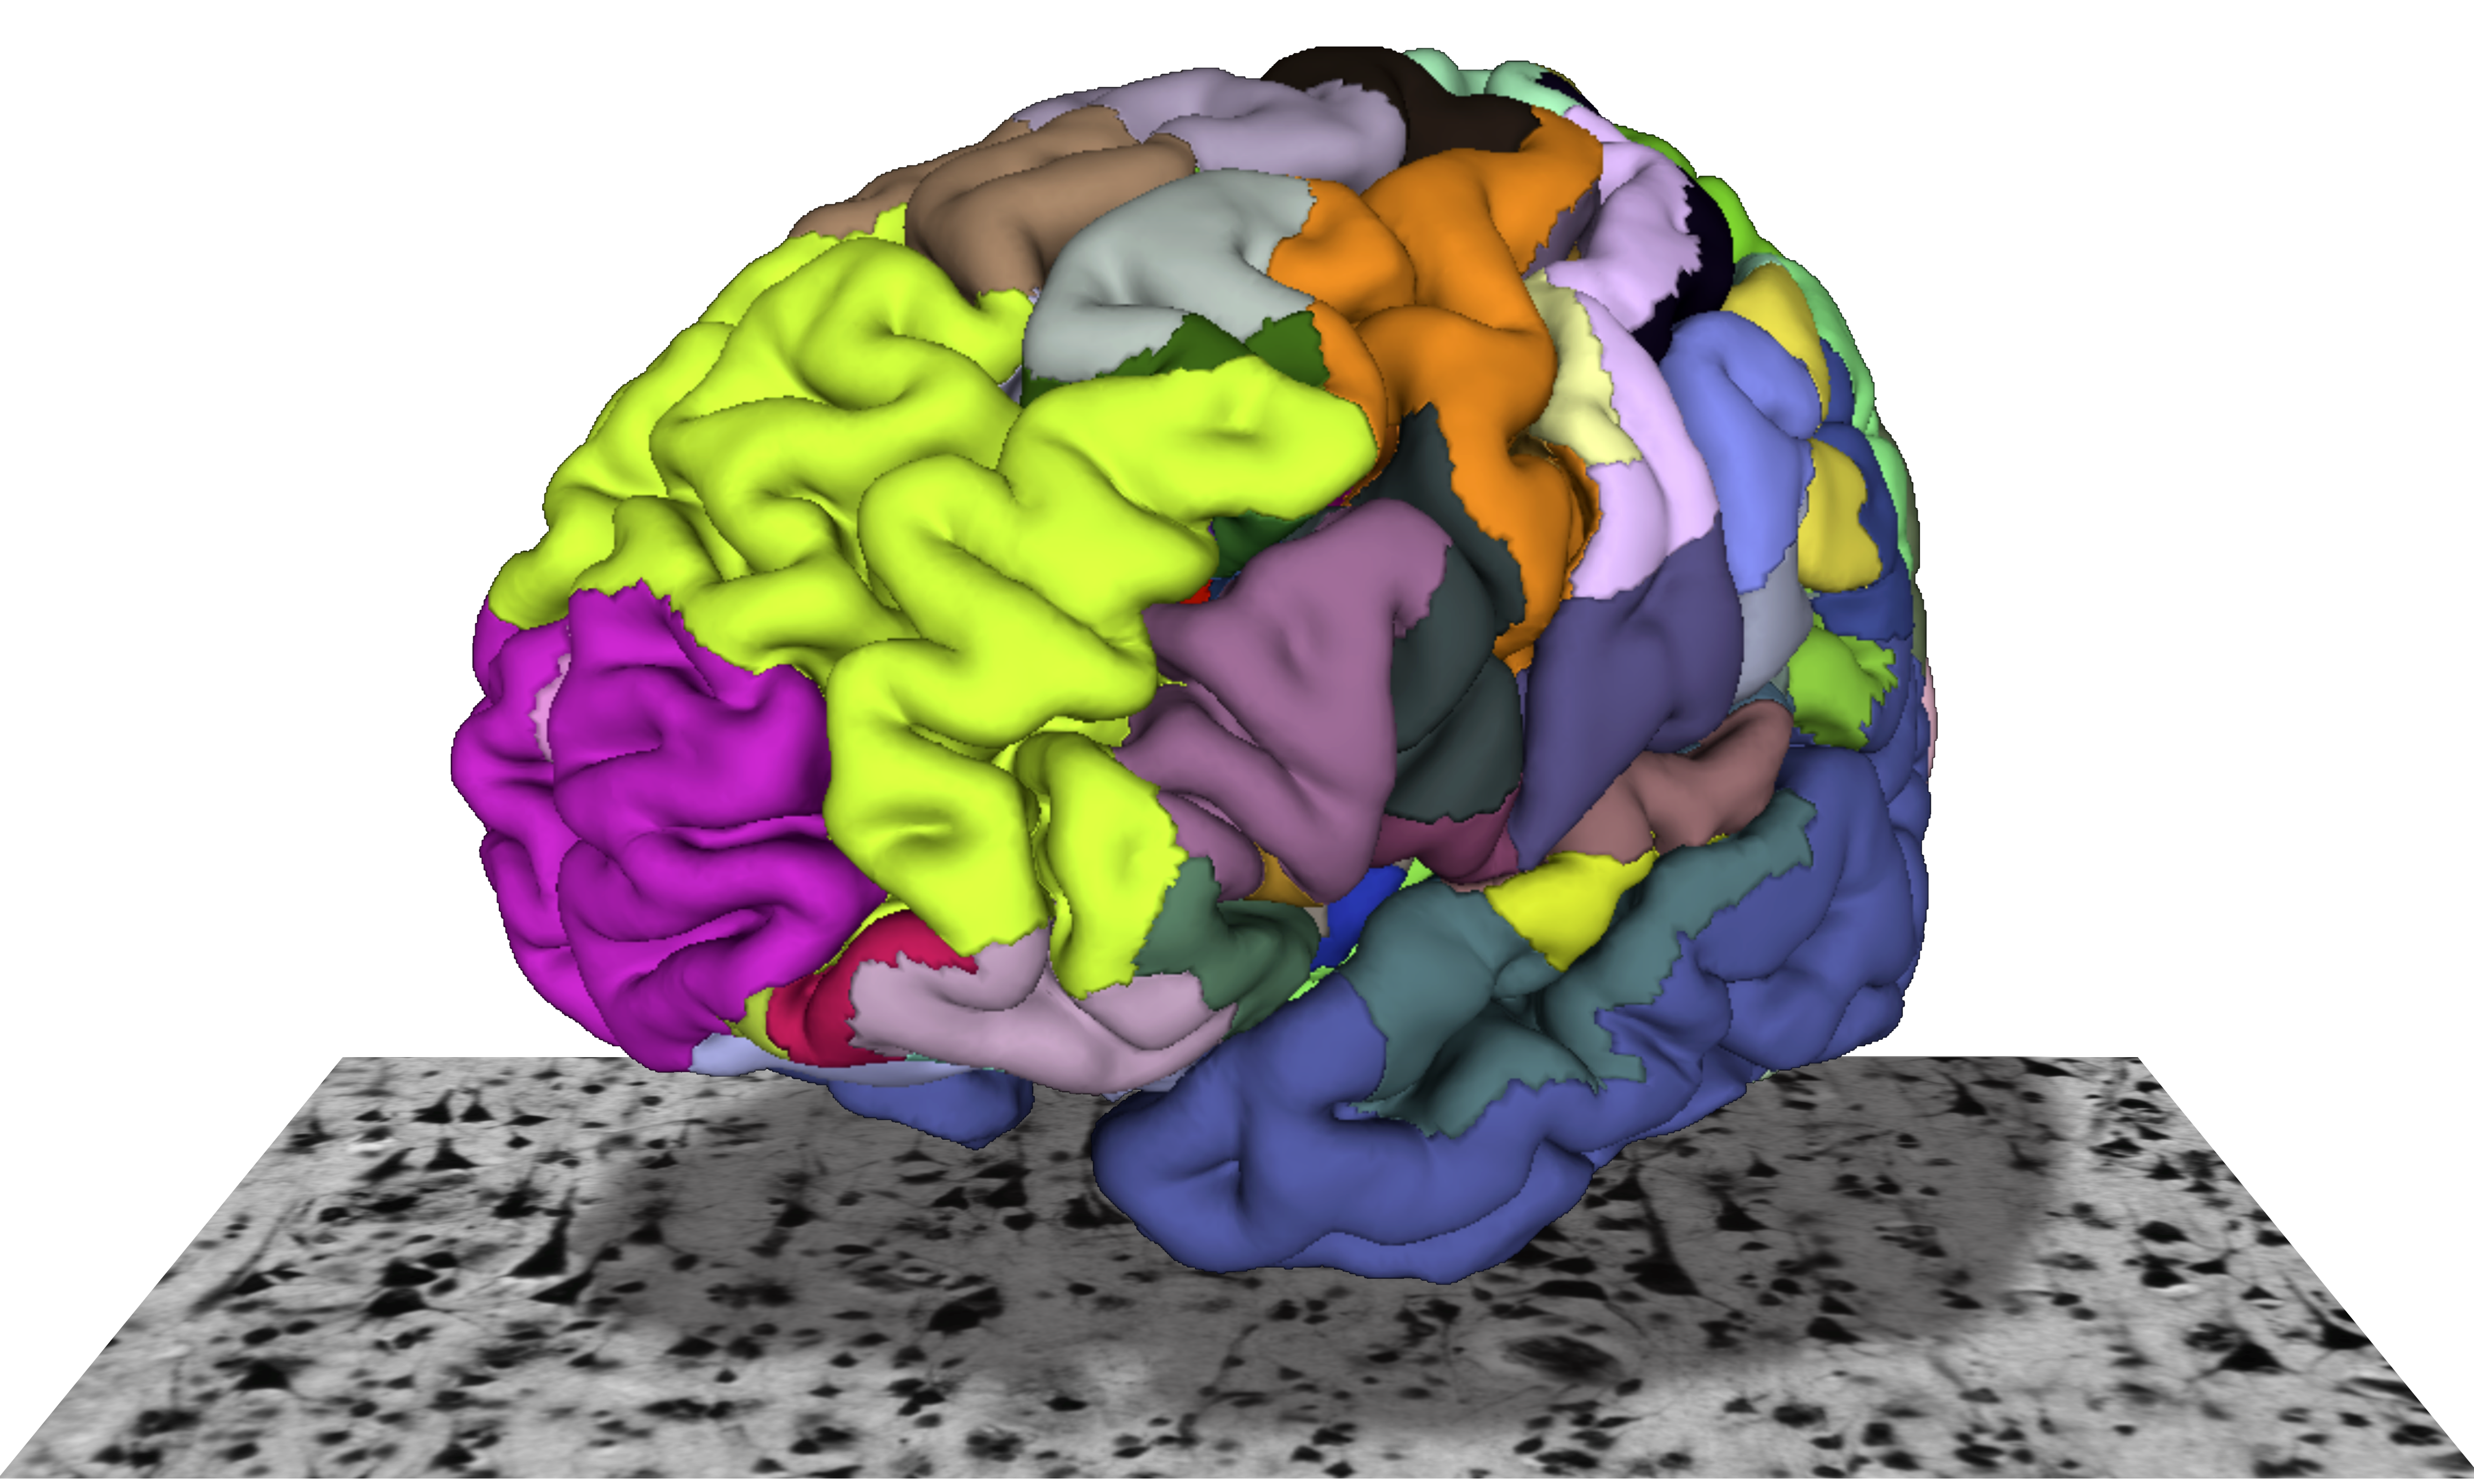

The institute division of Structural and Functional Organization of the Brain (INM-1) is developing a three-dimensional digital atlas of the human brain. For this purpose, areas of the cerebral cortex, subcortical core areas, as well as fiber webs in post-mortem brains are mapped. In order to do justice to the enormous complexity of the human brain, our approach consists in the integration of cyto- and receptorarchitectural, genetic and functional as well as PLI-based maps into a multi-modal atlas of the brain. For this purpose, we develop methods for image analysis and 3D reconstruction, artificial neural networks and big-data analysis with supercomputing.

The „BigBrain“, an ultra-high resolution brain model, and the Julich-Brain, a cytoarchitectural atlas reflecting variations in brain structure, are results of our research.We make our brain maps available to the scientific community. They are part of the HBP Human Brain Atlas and can be merged with neuroimaging data via the Anatomy Toolbox.